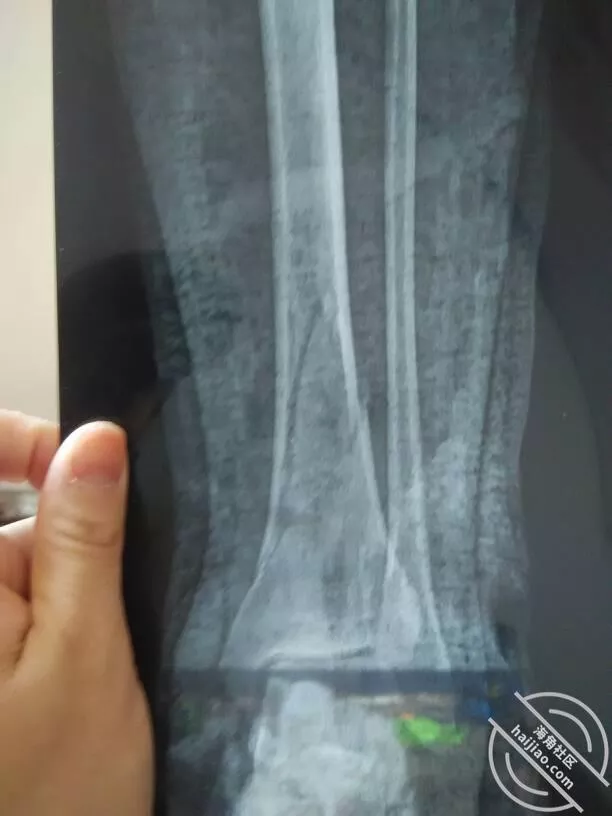

一位好心大哥开车拉我来到离得比较近的医院。期间我给表哥打了电话说了情况,他表示马上就赶来医院。挂号就诊后护士带我做了各种检查,检查诊断胳膊脱臼,腿骨骨折,身上多处擦伤。膊脱臼倒是好治疗,就是这个腿骨折了,需要动手术打钢钉,也可以打石膏等着自己愈合,时间就是慢些,效果也不如打钢钉好,但是手术需要等消了肿着才能做。